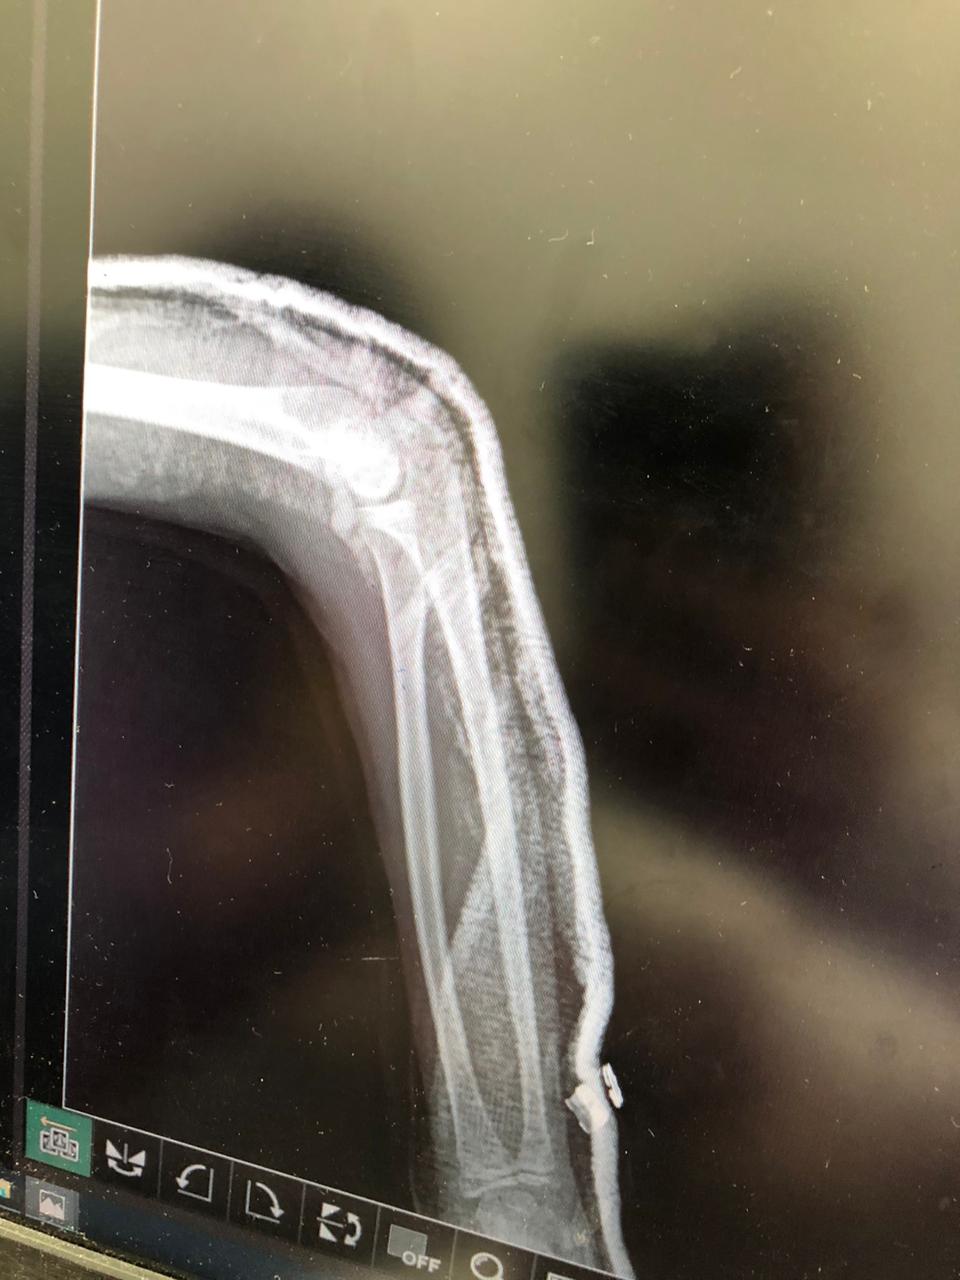

الم فى الذراع بعد الجبيره هل فيه مشكله فى الجبيره وقع على ذراعه وعملنا الاشعه ممكن توضيح للأشعة او تفسير للحاله